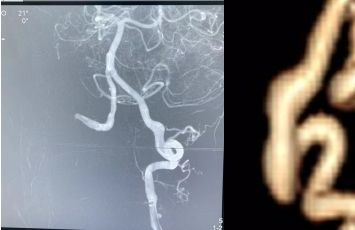

脑外科田垒医生接诊患者后建议患者入院治疗。入院后查体,患者神志清楚,对答切题,四肢活动好,无其他异常。董永军副主任查看患者后考虑为「脑血管疾病」,进一步行全脑血管造影明确诊断为「左侧椎动脉 V4 段夹层动脉瘤」。血管迂曲严重,椎动脉夹层动脉瘤所处位置在脑干附近,动脉瘤最宽处直径约 7 mm,长约 2 cm,一旦破裂凶多吉少。

脑外科针对患者病情迅速开通了绿色急救通道,由田德洲主任主持,经北医三院韩金涛教授,延安分院脑外科陈素华学术主任、董永军副主任各位专家远程讨论给出了最佳治疗方案,决定在全身麻醉下行 SurpassEvolve 血流导向密网支架植入术。